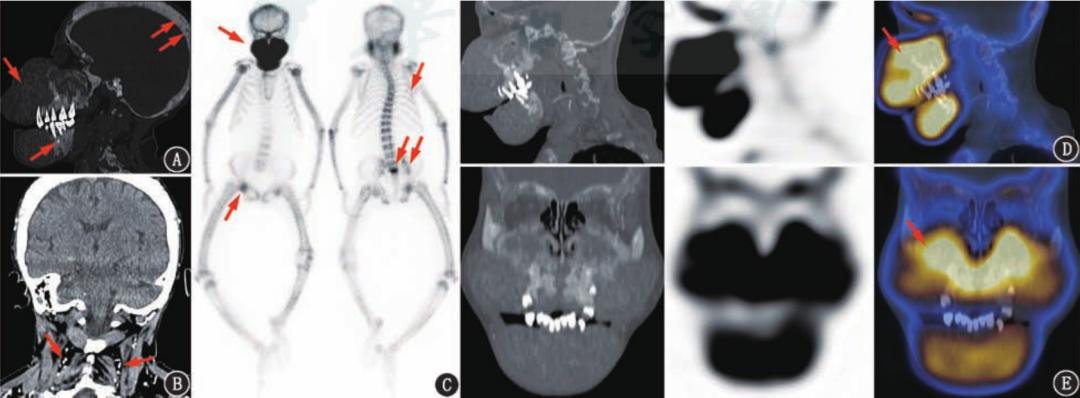

图片来源:Chronic kidney disease-mineral bone disorder: an update on the pathology and cranial manifestations. J Oral Pathol Med. 2015.

图片来源:尿毒症致退缩人综合征伴骨性狮面99Tcm-MDP SPECT/CT显像一例

从影像学检查,我们可以看得更清晰:上颌骨向前向下整体增大、下颌骨垂直向增大,导致面部向前突出、向下增大。

肾性骨病不仅会让人面容改变,全身各处骨骼都可能出现异常,甚至脊柱弯曲压缩,身高退缩,一米八变成一米五,需要拄拐才能行走。